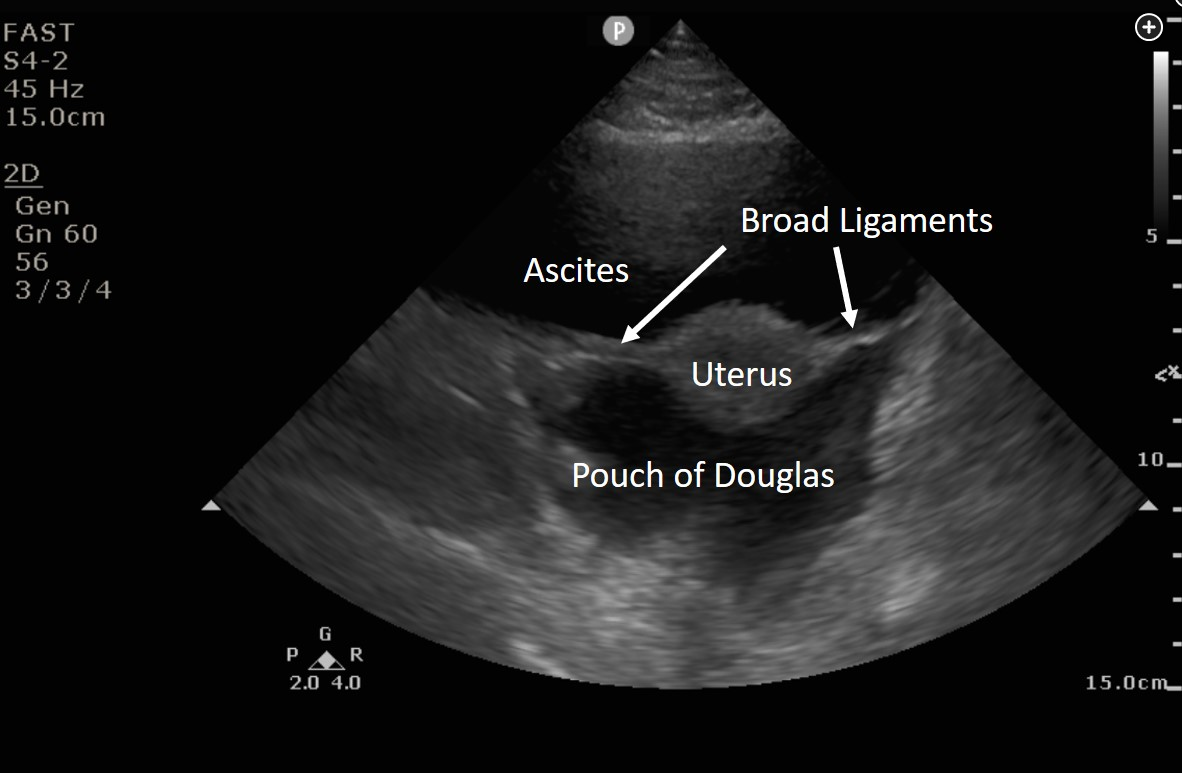

Interpretation of the FAST exam relies on knowledge of abdominal anatomy. Figure 2 is a transverse view just above the symphysis pubis showing the uterus suspended in anechoic fluid. The star is located posterior to the uterus in the pouch of Douglas, also called the rectouterine pouch (choice B is correct). The urinary bladder is located anterior to the uterus, not posterior (choice A is incorrect). The sigmoid colon should not present as an anechoic structure (choice C is incorrect). The bifurcation of the inferior vena cava should be much smaller than the area shown and would not be seen this close to the uterus (choice D is incorrect). Whenever there is doubt about whether an anechoic structure is vascular, color Doppler imaging can be helpful.123